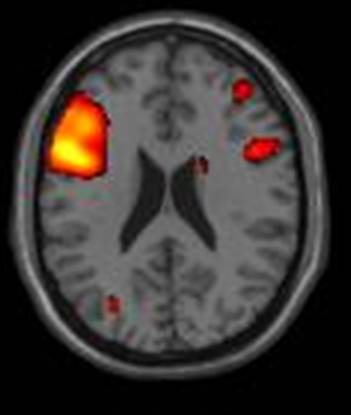

Bipolar Disorder, Mood disorders